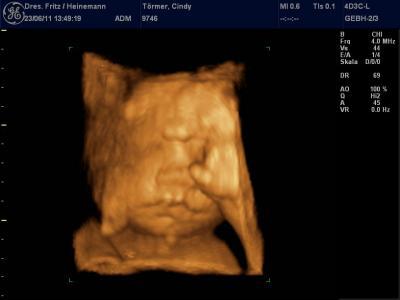

Das USBild ist von der 32. SSW

Möchte euch mal unser Baby zeigen :)